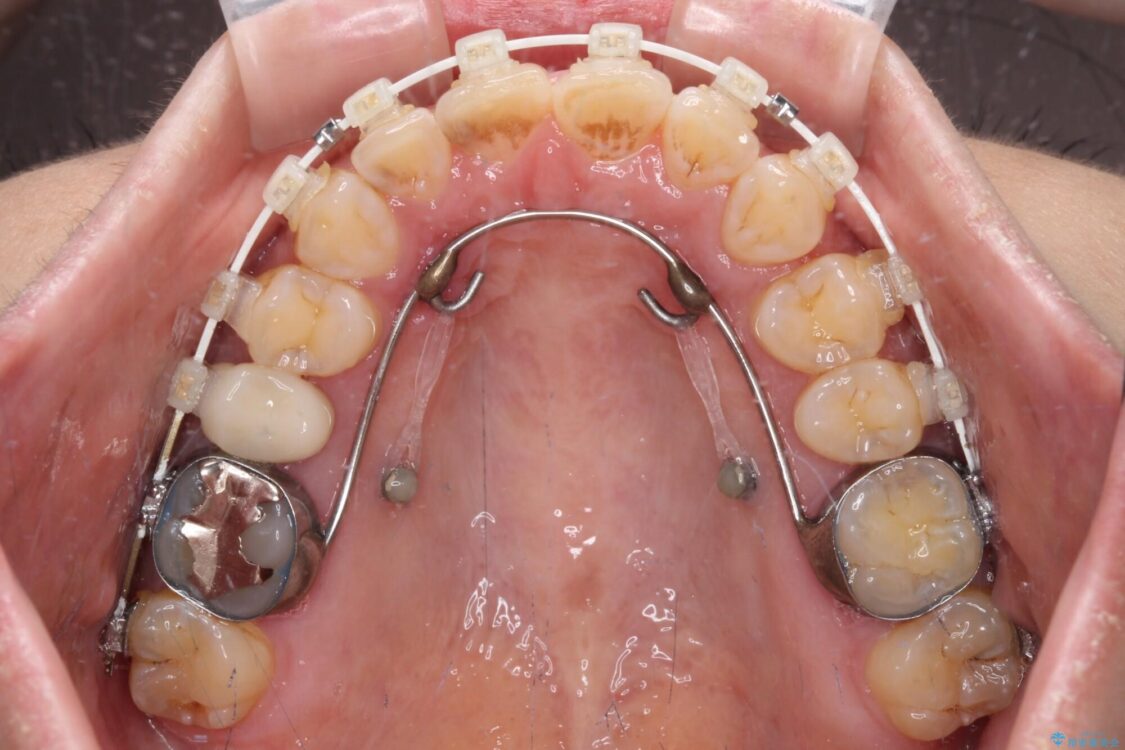

なるべく早めに治療を終えたいとのことで、補助装置を用いて上顎臼歯を後方に移動させ、同時にワイヤー装置にて整えることとしました。

治療途中

• 【モニター】飛び出た前歯を整えたい ワイヤー矯正治療 治療途中画像